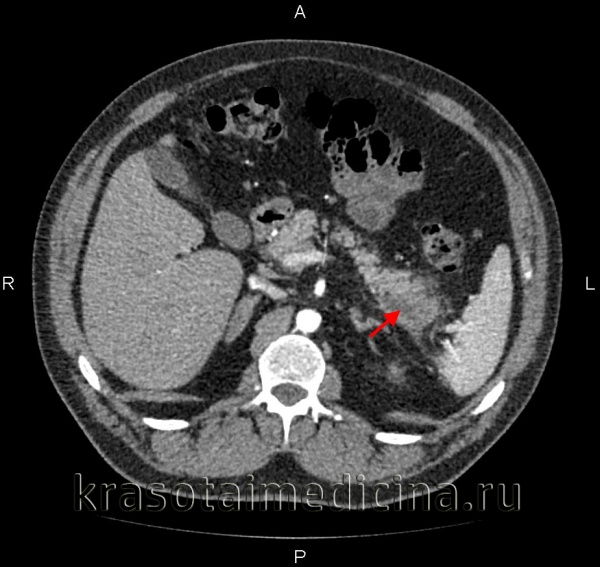

Наиболее информативными инструментальными методами диагностики острого панкреатита являются УЗИ, КТ, МРТ органов брюшной полости. УЗИ остается одним из наиболее доступных и информативных методов исследования. Эта безопасная неинвазивная методика позволяет выявить этиологический фактор острого панкреонекроза (конкременты желчевыводящих путей), отек и участки некроза поджелудочной железы, позволяет дифференцировать жидкостные образования. Но «золотым стандартом» диагностики на современном этапе является компьютерная томография органов брюшной полости. Данная методика позволяет четко визуализировать увеличение поджелудочной железы, очаги некроза, а также наличие осложнений, с высокой достоверностью разграничивать жидкостное скопление от плотных некротических масс. Наличие пузырьков газа в зоне деструкции, определяемое при КТ-исследовании, свидетельствует об инфицировании данного очага.

КТ органов брюшной полости. Панкреатит (в области хвоста поджелудочной железы) с наличием отека ее паренхимы, жидкостного содержимого вблизи ее края, на фоне утолщение фасции Героты слева

Компьютерная томография является более точным методом диагностики острого панкреатита по сравнению с УЗИ. Для проведения ее нет помех. Достоверность диагностики увеличивается при усилении контрастным материалом. Компьютерная томография с усилением позволяет более четко выявить диффузное или локальное увеличение размеров железы, отек, очаги некроза, скопление жидкости, изменения в парапанкреатической клетчатке, "дорожки некроза" за пределами поджелудочной железы, а также осложнения в виде абсцессов и кист.